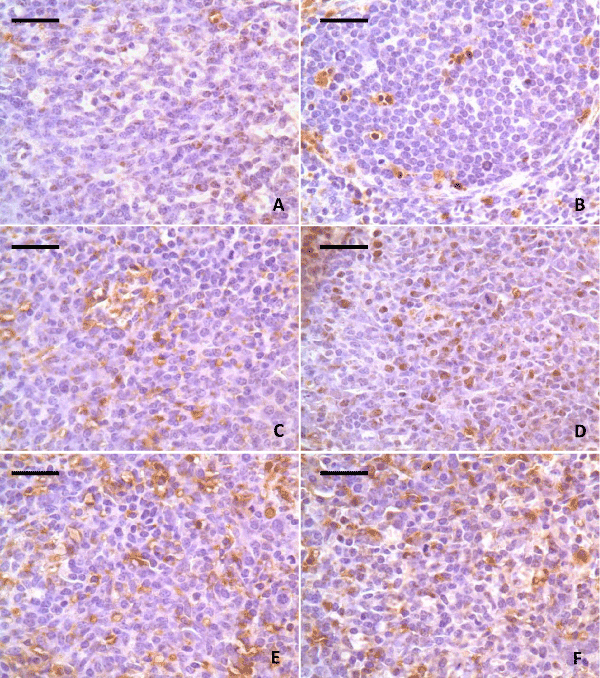

| Figure 2: The spleens are stained for Bax protein at 42 days of age. There are several positive splenocytes (brown-stain) in control group (A). The positive splenocytes is slightly increased in 5 mg/kg group (B) and markedly increased in 15 mg/kg, 30 mg/kg, 45 mg/kg and 60 mg/kg groups (C, D, E, F). SABC. Bar=20 μm. |